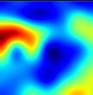

4.5. Explaining COVID-19

| X-ray | VGG16 | ResNet50 | Inception | Ensembled (Ours) | Uncertain-CAM (Ours) | Ground Truth |

![]() | ![]() | ![]() | ![]() | ![]() | ![]() | ![]() |